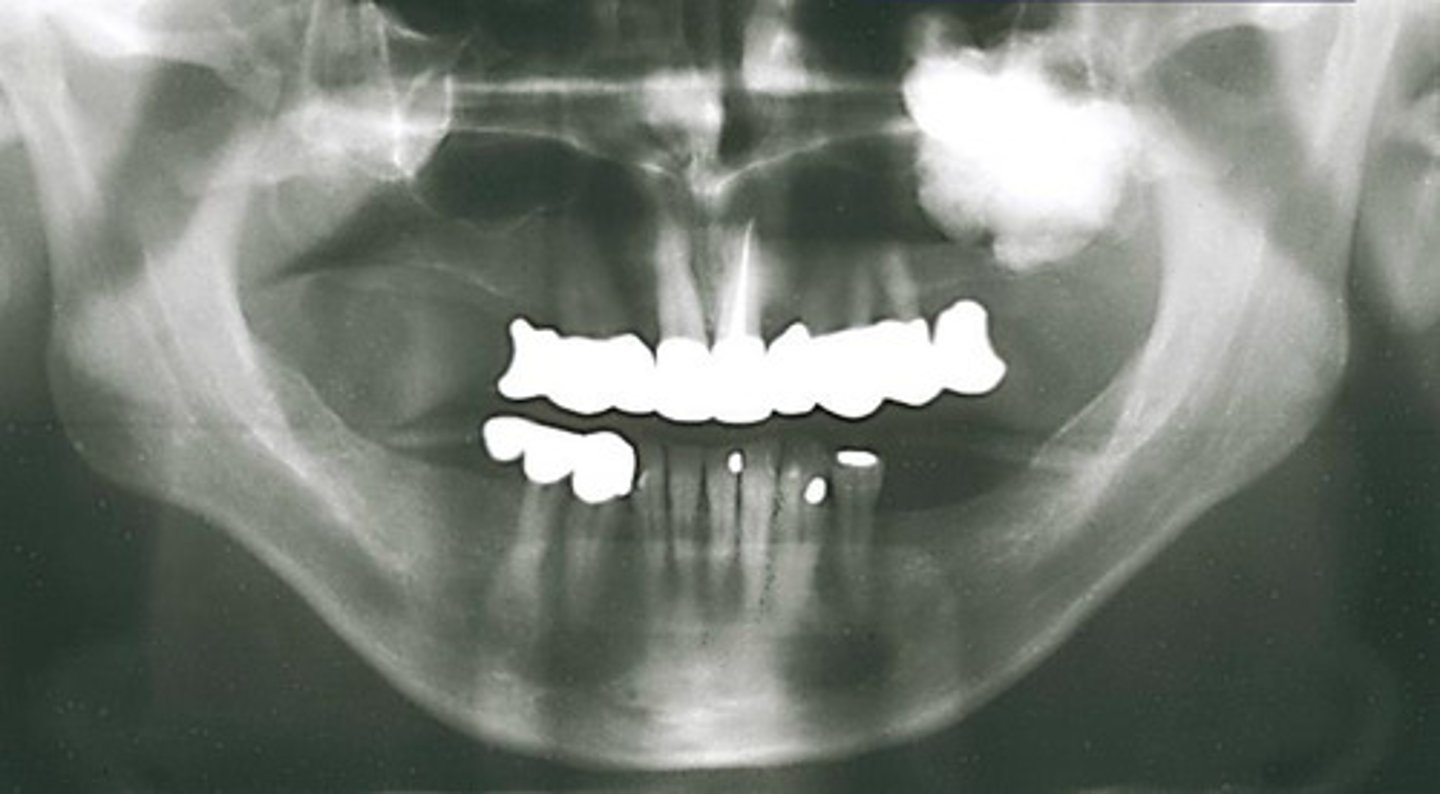

How would you describe the lesion?

- Ill defined, moth-eaten trabecular pattern in the entire mandible

- There is chronic periodontal bone loss associated with most mandibular teeth with furcation involvement and apical radiolucencies

- There is thinning of the inferior mandibular cortex.

- Can also be described as ill-defined areas of mixed radiolucent and radiopacities throughout the

mandible

What category would this lesion be part of?

Inflammation/Malignant

What would be a differential diagnosis for this lesion?

Chronic osteomyelitis

(DD: osteomyelitis, multiple myeloma)